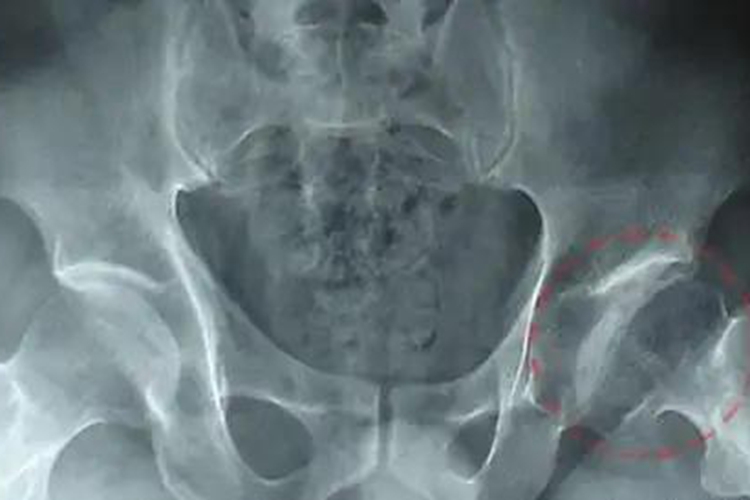

Ⅲ期(股骨头塌陷期)

X片提示股骨头负重区的软骨下骨呈不同程度的变平和塌陷,股骨头失去了圆而光滑的外形,软骨下骨的骨密度增高。关节间隙仍保持正常宽度。 Shenton线基本保持连续。